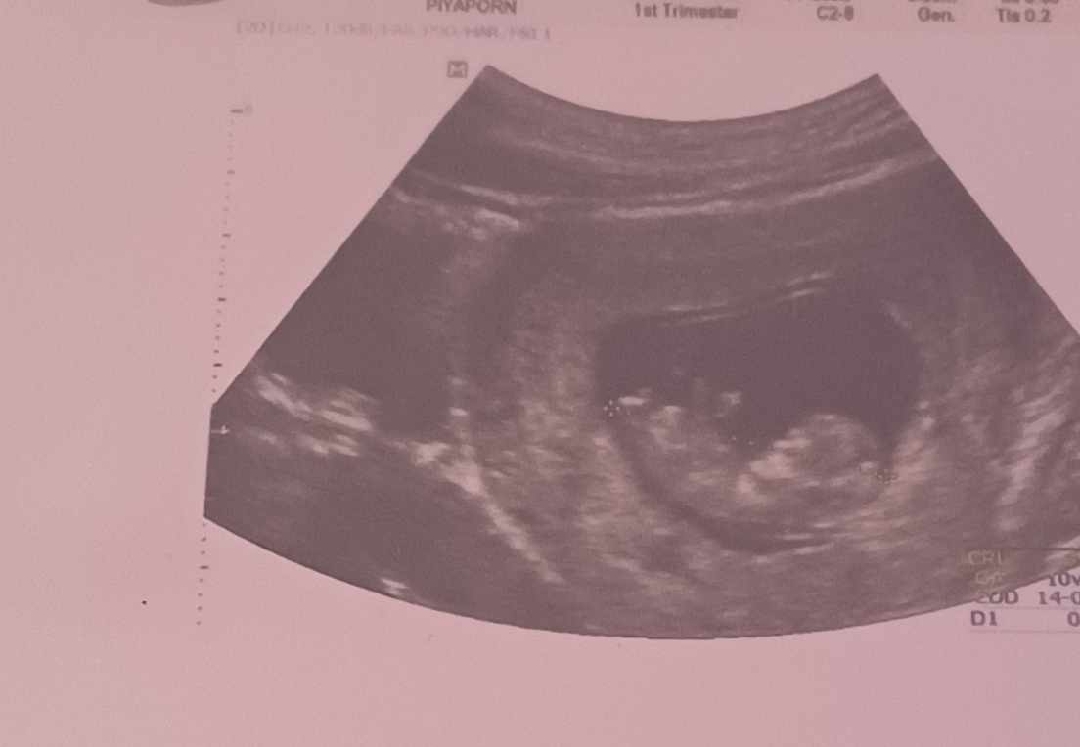

วันนี้แฟนได้ไปฝากท้องกับหมอครั้งแรกแต่ผมไม่ได้ไปด้วยเพราะติดงานด่วนเลยไม่รู้ว่าหมอบอกยังไงบ้างแต่แฟนส่งรูปมาให้ดูเลยอยากรู้ว่าประมาณนี้จะต้องดูแลยังไงต่อไปครับ